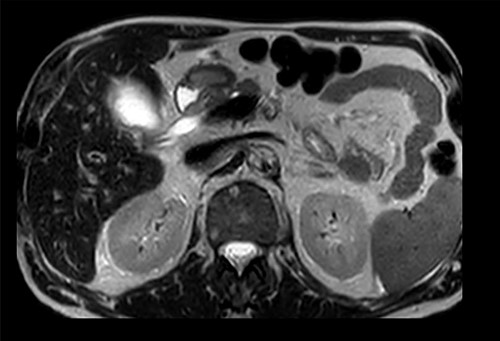

Subsequent review of preoperative imaging solved the mystery. Duplicated gallbladder with double cystic ducts was clearly evident on CT and magnetic resonance imaging (MRI) which were hidden in plain sight (Figs 4–7). CT cholangiogram (Fig. 3) was performed Day 1 post-operatively showing the double cystic duct with no evidence of bile leak. Rest of patient’s admission was uneventful and he was cleared for discharge on Day 5 post-operatively. Patient remains well and was back to his daily activities during his follow-up review.

Preoperative T2-weighted MRCP; double cystic ducts seen upon retrospective review of images post cholecystectomy.